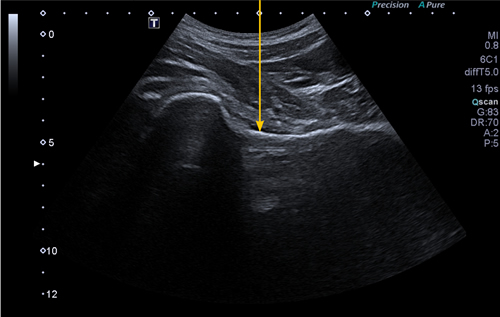

La viscosuplementación intrarticular fue estandarizada en todos los pacientes e independiente del AH empleado. En dicho procedimiento, realizado siempre por los mismos facultativos, se practicaba un abordaje ecoguiado por vía anterior a nivel infrainguinal. Mediante un equipo de ecografía Canon Xario 100G® y con la sonda cónvex de 5 MHz emplazada perpendicular al pliegue de la ingle, y desplazándola lateralmente a los vasos femorales, se identificaba un plano de seguridad que incluyera margen superior de la cabeza y cuello femoral, borde acetabular y recorrido de la cápsula articular hasta la zona cervical del fémur (Figura 1). Mediante el empleo del ecógrafo en su modo doppler podíamos identificar la ausencia de estructuras vasculares en ese plano de seguridad además de medir la profundidad del recorrido de la aguja. En este plano se identificaba el punto medio perpendicular al objetivo de la infiltración en la zona cervical, dentro de la cápsula articular (Figura 2). En ese punto se disponía una aguja espinal de 88 mm y 22 G, en dirección perpendicular al plano de la camilla, desplazándola hasta contactar con el cuello femoral. A continuación se retiraba unos milímetros y se procedía a una aspiración amplia para volver a asegurar la ausencia de estructuras vasculares y eventuales inyecciones intravasculares. Posteriormente se inyectaba el contenido de cada formulación de AH, y se retiraba la aguja colocando un apósito. Todo ello realizado con las adecuadas normas de esterilidad y asepsia. A cada uno de los pacientes se les recomendaba un reposo relativo de 24 horas tras la técnica.

Fig. 1. Imagen de guía ecográfica de la infiltración intrarticular de la cadera, identificándose la cápsula articular en la transición cefálico-cervical del fémur, objetivo para la disposición de la aguja e introducción del producto infiltrado.